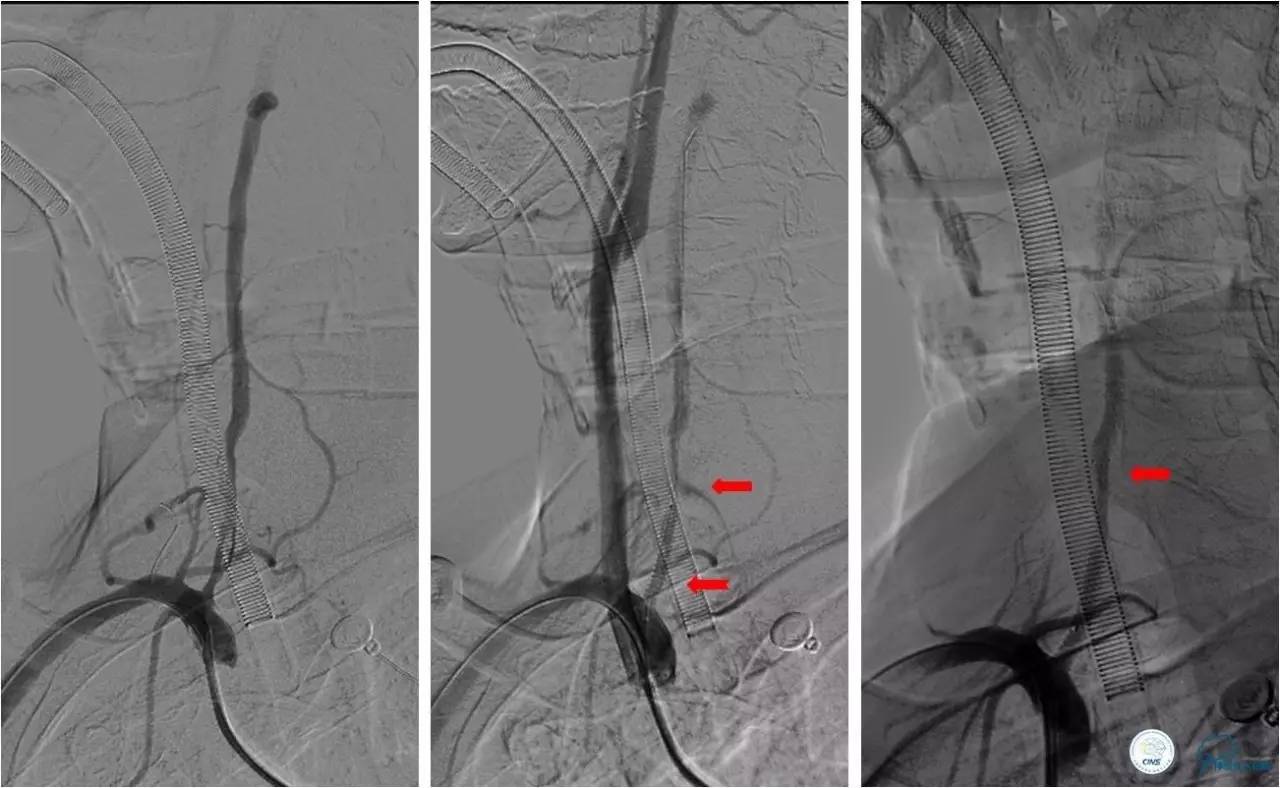

》治疗过程

★2.0x20 mm球囊扩张后,右椎动脉起始段见前向血流,将6F navien颅内支撑导管送至V3段造影,见V4段有血栓,基底动脉闭塞 ;

★Solitaire 6.0x20 mm取栓支架到位造影,取栓两次后基底动脉再通。

★取栓后处理椎动脉起始端的狭窄,椎动脉开口处先放置一枚球扩支架,造影见支架远端仍有狭窄,将Solitaire 6.0x20 mm贴敷在狭窄段,造影见前向血流改善(TICI分级 3级)。